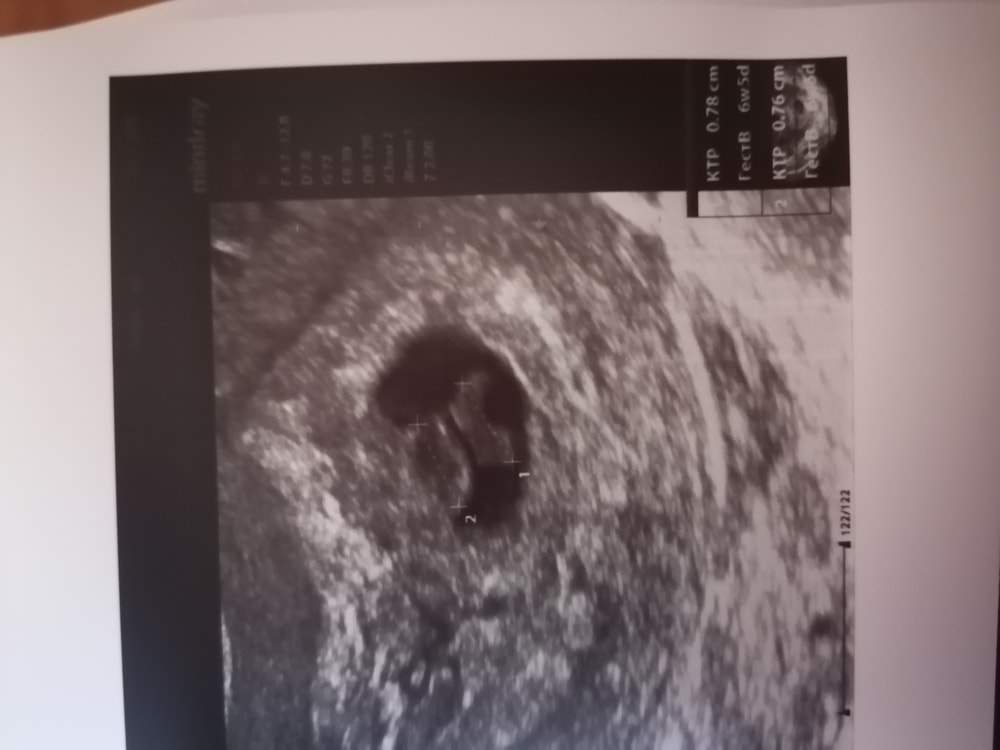

Обследования, узи, анализыБыла на УЗИ сегодня, недовало мне покоя что только пя было 2 сентября

Делают узи все на данный момент хорошо, гематом на данный момент нет, больше какое-то как изменение эндометрия, но говорить что это отслойка или гематома говорить не могут так как это может быть и вариант нормы

Но нашли и 2!!!!! Они как вальтом стоят по сроку тоже самое но ср не нашли но трепетание есть

Но даже если у 2 не будет ср+ это все нормально будет хоть один но я в шоке!!!!!!